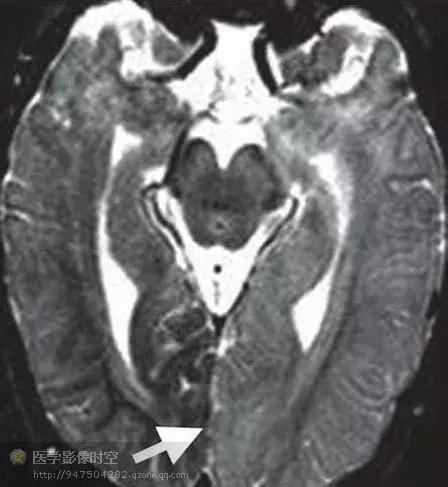

一侧巨脑症

一侧巨脑症是一种严重的罕见皮层发育不良,Sims于1835年首次报道。可以单独发生,也可以伴发于多种综合症,包括神经纤维瘤病Ⅰ型,结节硬化,表皮痣综合征,黑色素过少症。病理学特征是一侧大脑半球部分或者全部错构瘤样过度生长,目前认为是不明原因引起的增殖和分化异常。临床上主要表现为严重的抗药性癫痫。其它的常见表现包括巨颅、智力低下、一侧运动功能不全、一侧偏盲,提示受累皮层无功能。建议早期一侧大脑切除,或者一侧大脑切除。

一侧巨脑症具有典型的磁共振成像特征。最显著的特征是单侧皮层增厚,累及部分或者全部大脑半球。受累大脑半球也显示继发于髓鞘化过度的单侧白质改变,这取决于具体的髓鞘化程度。也可以单侧基底节和嗅束的错构瘤样受累。另外,也常见单侧侧脑室增大。神经影像学新技术例如扩散张量成像和MR-PET融合图像也可以提供更多的认识。扩散张量成像和纤维示踪图提示异常的大脑半球过度髓鞘化,表现为局部的水分子扩散的各向异性不对称性升高(图9b,c)。发作期MR-PET融合图像可以清晰显示受累大脑半球的不对称性高代谢区。

图9 难治性癫痫病人的右侧的一侧性巨脑症。

图9a横断T2WI显示巨脑回和右侧皮层增厚(箭头)以及异常的邻近白质低信号(箭)

图9b横断扩散张量成像显示右侧前额叶髓鞘化程度过高(箭),与异常的T2WI高信号相对应。

图9c纤维示踪图显示右侧大脑半球较多侧神经纤维束更多。

图9d横断发作期MR-PET融合图像显示右侧额叶在癫痫发作期间为高代谢区(箭)